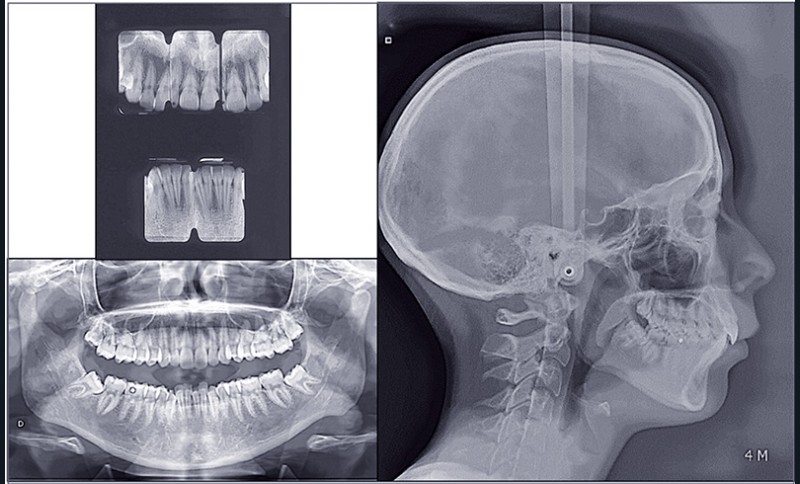

Traitement orthodontico-chirurgical multiattaches maxillaire et mandibulaire avec extraction de 15 25 34 44 et avancée mandibulaire chirurgicale. Le traitement a été réalisé en technique de Tweed avec…